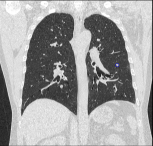

Chẩn đoán hình ảnh mô mềm tiên tiến cho vùng bụng.

Tăng cường độ tương phản I-ốt.

Hỗ trợ đánh giá an toàn cho bệnh nhân.

Đảm bảo hình ảnh chất lượng cao.